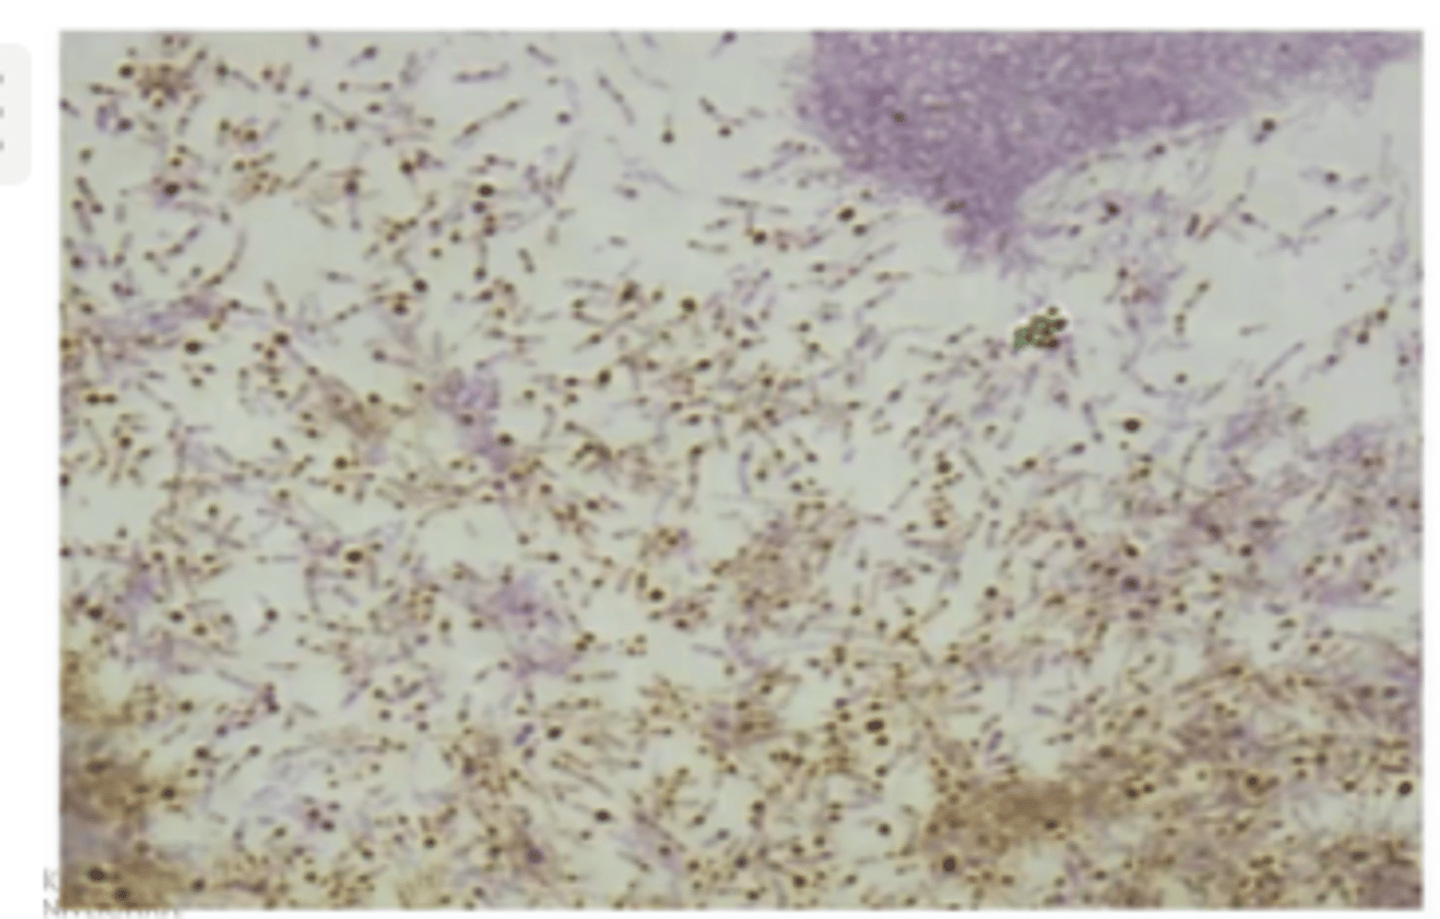

Cīla-Nēlsena metode - kad tiek izmantota?

- tiek izmantota skābju rezistentām baktēriju krāsošanām (piem., mycobacterium tuberculosis)

- pacienta materiāls - krēpas

Cīla-Nēlsena metode - process

1. Fiksētam preparātam uzliek filtrpapīru, uzlej koncentrētu karbolfuksīna šķīdumu.

2. Karsē virs spirta lampas liesmas, līdz parādās tvaiki.

3. Atkrāso ar 5% sērskābes šķīdumu vai spirta un sālsskābes maisījumu. (atkrāsojas viss, izņemot mycobacterium tuberculosis, jo tā ir skābju rezistenta - ar skābēm to nevar atkrāsot).

4. Metilēnzilo krāso 2 min